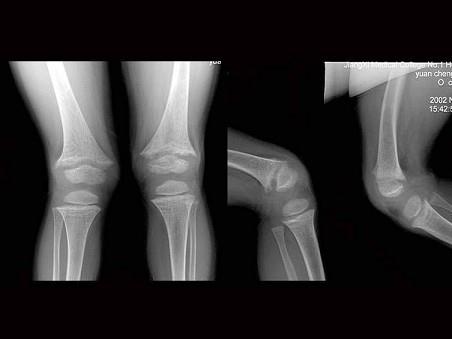

男,6岁,身材矮小,关节畸形,血钙磷化验异常,如图,最可能的诊断为?(?)A.坏血病B.肾性佝偻病C.粘多糖病D.克汀病E.脂质沉积病

问题 男,6岁,身材矮小,关节畸形,血钙磷化验异常,如图,最可能的诊断为?(?)

选项 A.坏血病 B.肾性佝偻病 C.粘多糖病 D.克汀病 E.脂质沉积病

答案 B